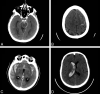

Results: Two hundred thirty patients (mean age, 54 years; 51% male) with CTA-negative SAH were identified. The pattern of SAH was diffuse (40%), perimesencephalic (31%), sulcal (31%), isolated IVH (6%), or identified by xanthochromia (7%). Initial DSA yield was 13%, including vasculitis/vasculopathy (7%), aneurysm (5%), arteriovenous malformation (0.5%), and dural arteriovenous fistula (0.5%). An additional 6 aneurysms/pseudoaneurysms (4%) were identified by follow-up DSA, and a single cavernous malformation (0.4%) was identified by MRI. No cause of hemorrhage was identified in any patient presenting with isolated intraventricular hemorrhage or xanthochromia. Diffuse SAH was due to aneurysm rupture (17%); perimesencephalic SAH was due to aneurysm rupture (3%) or vasculitis/vasculopathy (1.5%); and sulcal SAH was due to vasculitis/vasculopathy (32%), arteriovenous malformation (3%), or dural arteriovenous fistula (3%).

Conclusions: DSA identifies vascular pathology in 13% of patients with CTA-negative SAH. Aneurysms or pseudoaneurysms are identified in an additional 4% of patients by repeat DSA following an initially negative DSA. All patients with CT-negative SAH should be considered for DSA. The pattern of SAH may suggest the cause of hemorrhage, and aneurysms should specifically be sought with diffuse or perimesencephalic SAH.